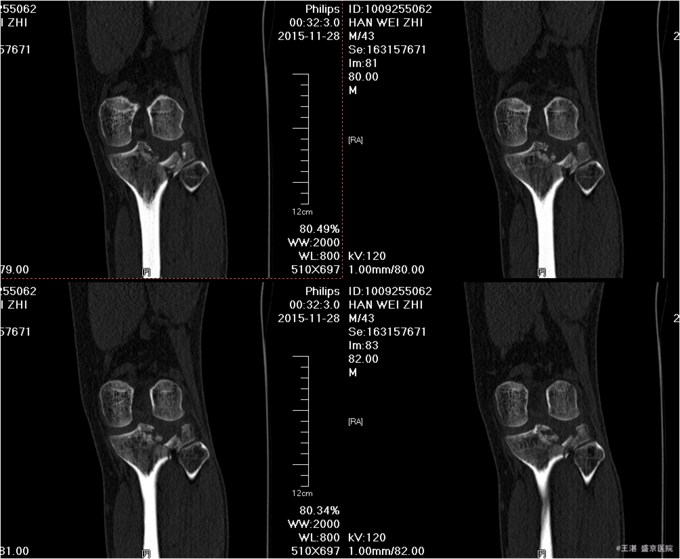

患者及家属自诉于2015年11月28日晚9点在沈阳市铁西区自己摔倒,摔倒后左下肢疼痛,活动受限,不能活动,急送至沈阳八院急诊,行DR提示:左胫骨近端粉碎性骨折。后送至我院急诊,行左膝关节CT后以“左胫骨近端粉碎性骨折”为主要诊断收入我科。患者轮椅入病房,无发热,无头晕头迷,无胸闷气短,无心慌心悸,无腹痛腹胀,受伤后排气正常,大小便未排。

专科查体:患者轮椅入病房。左小腿活动受限,压痛(+),叩击痛(+),双下肢皮肤感觉正常,足背动脉可扪及搏动,末梢血运良好,足趾活动灵活。 辅助检查:左膝关节CT:(我院,2015-11-29):左胫骨近端粉碎性骨折。